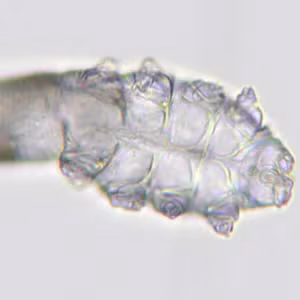

A 25-year-old woman had a few mildly scaly lesions on her forehead. She saw her physician and initially it was thought that she had a fungal lesion. Figure A-C show what was seen in skin scrapings from the lesion. The object shown was approximately .25mm long. What is your diagnosis? Based on what criteria?

Figure A